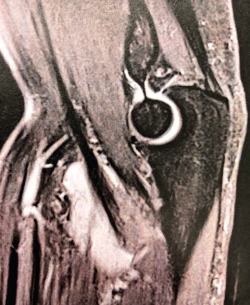

La bursitis es típicamente hipointensa en T1 con realce tras la administración de gadolinio y presenta halo periférico en T2. La RNM es especialmente útil en el diagnóstico diferencial de la bursitis con otras entidades que generan efecto masa en la fosa antecubital(26). Aunque las secuencias y posiciones típicas de la RNM suelen ser suficientes para realizar una valoración correcta del bíceps distal (Figura 4), existe la posición llamada de FABS (flexed, abducted, supinated) que proporciona una imagen longitudinal del tendón desde la unión miotendinosa hasta su inserción en la tuberosidad radial en un solo corte(27). El paciente se coloca en decúbito prono, con el codo en flexión de 90°, el hombro en abducción máxima y el antebrazo en supinación máxima, permitiendo identificar y cuantificar lesiones parciales, roturas completas y tendinosis, y siendo de gran utilidad en aquellos pacientes con una constitución física que dificulte la correcta exploración física.

Figura 4. Corte sagital de resonancia nuclear magnética en el que se identifica una rotura completa del tendón del bíceps distal con 2 cm de retracción.